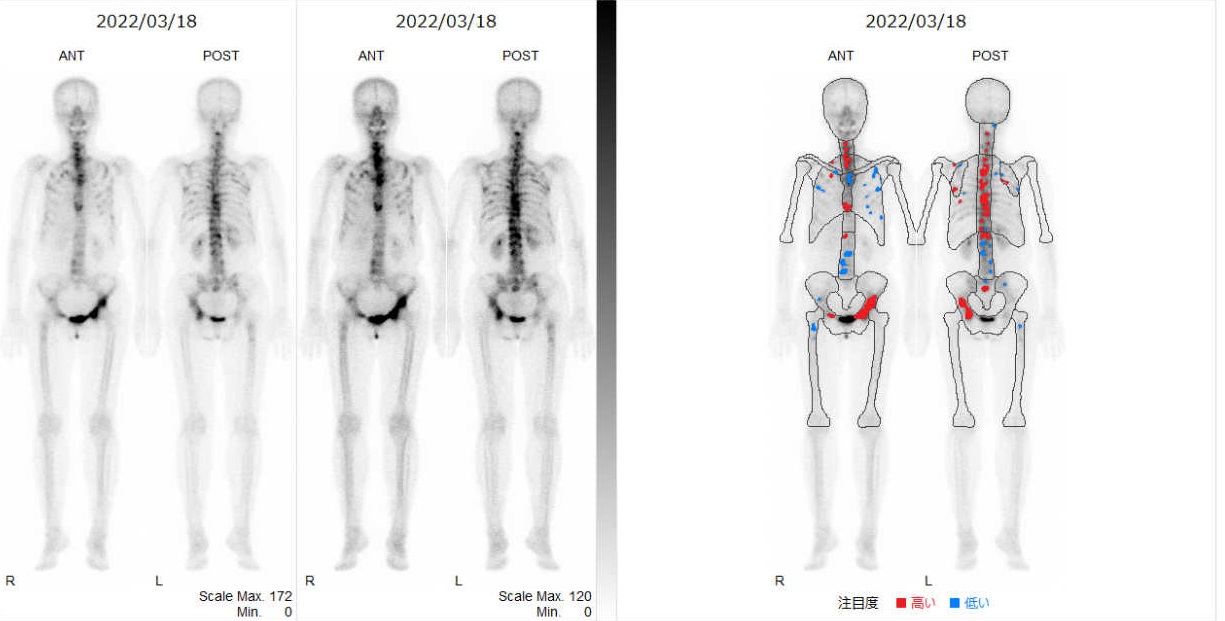

核医学検査

核医学検査は放射性同位元素を用いた画像検査です。がん診療においては転移箇所の検索に行われます。骨シンチグラフィ検査は、骨の代謝を画像化することができ、骨への転移を比較的早期に見つけることができます。

PET-CT検査

PET-CT検査は、病気の存在を見つける存在診断と広がり診断、病気の進行時期の診断、病気が良性か悪性かの診断、全身への転移を調べることのできる検査です。治療効果の判定、再発の確認もできます。体内でのブドウ糖代謝を利用した検査です。がん細胞は正常な細胞に比べ多くのブドウ糖を取り込みます。ブドウ糖の様に細胞に取り込まれる放射性同位元素を注射し、薬剤の分布を画像化します。

ブドウ糖代謝が活発な臓器(脳、心臓、消化管など)や泌尿器(腎臓、尿管、膀胱、尿路)はPET検査による診断が難しいことがあります。

PET検査(右肺がん)

PET-CT検査画像(右肺がん)

乳房専用PET検査画像(両側乳がん)